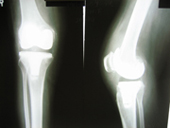

Arthritis both knees varus deformity pre op Post op Total Knee Replacement Post op Total Knee Replacement